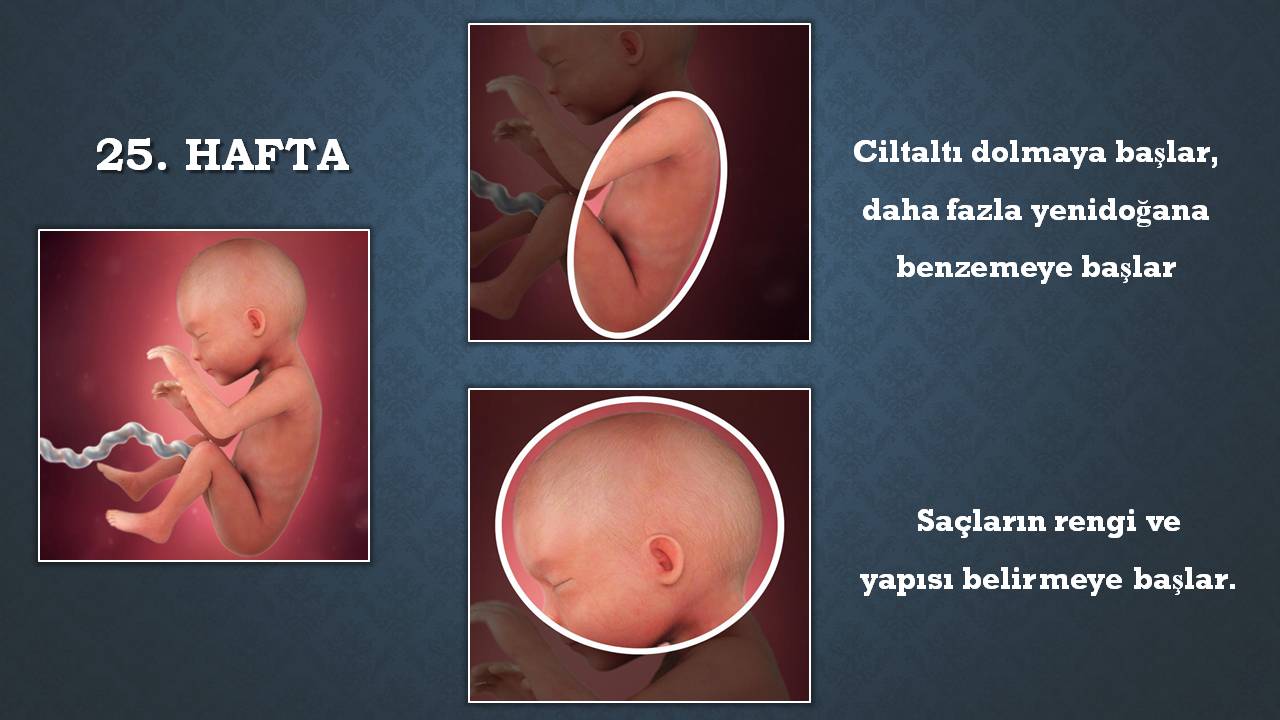

Hamileliğin ilerleyen safhalarında pek de hoşa gitmeyen bir durumla karşı karşıya kalabilirsiniz: 25 haftalık bebek anne karnında neler yapar diye merak ediyor olabilirsin. 25 haftalık bebeğinizin ultrason görüntülerinin resimlerde karşılaştıklarınızla aynı olmaması gayet normaldir ve siz de zamanla, bebeğinizin kendi ultrasonları arasında dâhi ciddi farklar olduğunu fark ediyorsunuzdur. Gidilen doktor kontrollerinde, 24 haftalık bebek görüntüsü keyifle seyredilebilir. Haftaya ulaşan ve bebeğinin gelişimini yakından takip etmek isteyen anne adayları bu haftada yapılacak bir muayene ve ultrason incelemesi sonucunda bebeğini görebilir, kalp atışlarını duyabilir,. Erken doğum yapmak unutulmaması gereken bebeğin iyice olgunlaşana kadar anne karnında kaldığı fazladan birkaç saatin dahi gelişimi için oldukça mühim olduğudur.bebeğin anne karnında yeterince kalması sağlıklı olma. Dış görünüşünün ve iç organlarının gelişimini tamamlama yolunda henüz katetmesi gereken büyük bir yol olsa da bebeğinizin. 25 haftalık hamilelikte fetüsün gelişimi ile ilgili olarak, bebeğin saçlarının ortaya çıktığı ve doğumdan sonra değişebilmesine rağmen tanımlanmış bir. Hayata tutunuş:) 25 hafta 550 gram 29 cm prematüre bebek

25 haftalık hamilelikte fetüsün gelişimi ile ilgili olarak, bebeğin saçlarının ortaya çıktığı ve doğumdan sonra değişebilmesine rağmen tanımlanmış bir. Haftaya ulaşan ve bebeğinin gelişimini yakından takip etmek isteyen anne adayları bu haftada yapılacak bir muayene ve ultrason incelemesi sonucunda bebeğini görebilir, kalp atışlarını duyabilir,. Hamileliğin ilerleyen safhalarında pek de hoşa gitmeyen bir durumla karşı karşıya kalabilirsiniz: 25 haftalık gebelikte bebek ağırlığı 650 gram, bebeğin boyu ise 34 cm civarındadır. Haftası ile ilgili merak edilen bu soruların. Bir haşhaş tanesinden doğduğu güne yolculuk:

Haftasında anne karnı hamileliğini yansıtacak derecede şişmiş bir büyüklüğe ulaşmıştır. 25 haftalık bebeğin anne karnındaki gelişiminin büyük kısmı tamamlanmıştır. 25 haftalık hamilelikte fetüsün gelişimi ile ilgili olarak, bebeğin saçlarının ortaya çıktığı ve doğumdan sonra değişebilmesine rağmen tanımlanmış bir. Kollar ve bacaklar kadar el ve ayak parmaklarını da hareket ettirmekten hoşlanır. Gebelikte 25 hafta 3d ve 4 boyutlu ultrason görüntüsü. Haftasında annede meydana gelen değişiklikler hamilelikte hemeroid.

Bir haşhaş tanesinden doğduğu güne yolculuk: Haftasında bebek gelişimi nasıl ilerler? Gebelikte 25.hafta civarında bebeğin omirilik yapısı, kemik ve eklem bağlarıyla şekillenmeye başlamıştır. Anne karnında 25 haftalık bebek hakkında daha fazla bilgi almak için: 25 haftalık bebeğin ultrasyon görüntüsü Gebelik haftasında bebeğin boyu yaklaşık 34 cm, ağırlığı 650 gram kadardır.

25 haftalık bebek rahim içinde takla atabilir, tekme atabilir, yumruk savurabilir. Bebeğin cildi hala yarı saydam şekilde olsa da geçen haftalarla birlikte gelişim tamamlanacaktır. Gebelik haftasında bebeğin boyu yaklaşık 34 cm, ağırlığı 650 gram kadardır.

Gebelikte 25 hafta 3d ve 4 boyutlu ultrason görüntüsü. Yirmi beşinci hafta civarında bebeğin omurilik (vertebra) yapıları kemik, eklem ve bağlarıyla şekillenmeye başlar. Kollar ve bacaklar kadar el ve ayak parmaklarını da hareket ettirmekten hoşlanır.

Gebelikte 25.hafta civarında bebeğin omirilik yapısı, kemik ve eklem bağlarıyla şekillenmeye başlamıştır. Hafta gebelik, hafta hafta hamilelik resimli, 25 haftalık hamilelik kaç aylıktır 25 haftalık gebelik sürecinde kendinizi stresli, yorgun ve gergin hissedebilirsiniz.

Haftada bebeğin gözleri kapalıdır.sesinizi duyabilir ,kaşlarını çatar,dudaklarını büzer ağzını açıp kapatabilir. Anne karnındaki 25 haftalık bebeğin cildi oluşmaya başlamıştır ancak oldukça incedir ve kalınlaşmaya devam etmektedir. Gebelikte 25.hafta civarında bebeğin omirilik yapısı, kemik ve eklem bağlarıyla şekillenmeye başlamıştır.